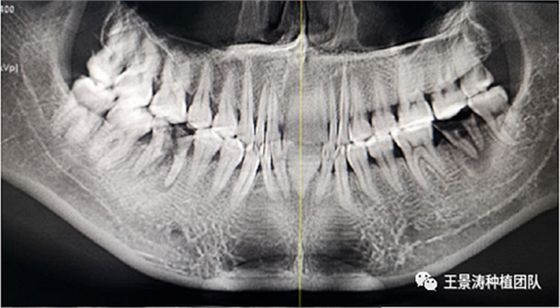

左側(cè)下頜第二磨牙及右側(cè)下頜第一磨牙同時(shí)即刻種植病例?;颊吣贻p女性,無系統(tǒng)性疾病。37及46殘冠及殘根,且46劈裂,無法冠修復(fù),必須拔除。37根尖慢性炎癥,大量肉芽組織存在,46根分叉較高,根分叉骨質(zhì)尚可。CBCT示:根尖骨質(zhì)至下牙槽神經(jīng)管距離可滿足種植體的初期穩(wěn)定性,遂考慮即刻種植,并在種植體周邊填入骨粉并覆蓋骨膜,雙側(cè)的種植體初期穩(wěn)定性相差無幾,但考慮到37根尖慢性炎癥較大,遂給予埋入式種植。

患者左側(cè)16慢性根尖周炎,17缺失。16根尖炎癥距上頜竇底較近,需內(nèi)提升,但是因?yàn)閮?nèi)提升后骨質(zhì)較薄所致植入深度過深,埋入式植入。17非埋入式種植。后期效果均可。